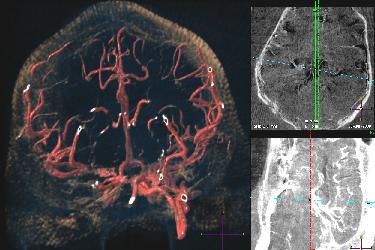

Mission: NECSTR is a neuroradiology facility that offers the latest technology in image guided intervention to support University investigators in developing minimally invasive treatments.

NECStR has been fully operational since May 3 2007 with a special focus is on image guided interventions for minimally invasive treatment of vascular disease. The center’s expertise and resources enable animal modeling of vascular pathologies, 3D x-ray imaging, post acquisition image processing, rapid prototyping from medical imaging and image guided minimally invasive surgery. Although the center’s focus lies in cardiovascular imaging and intervention, previous work has included selective vascular drug delivery for cancer treatment and orthopedic device implantation.